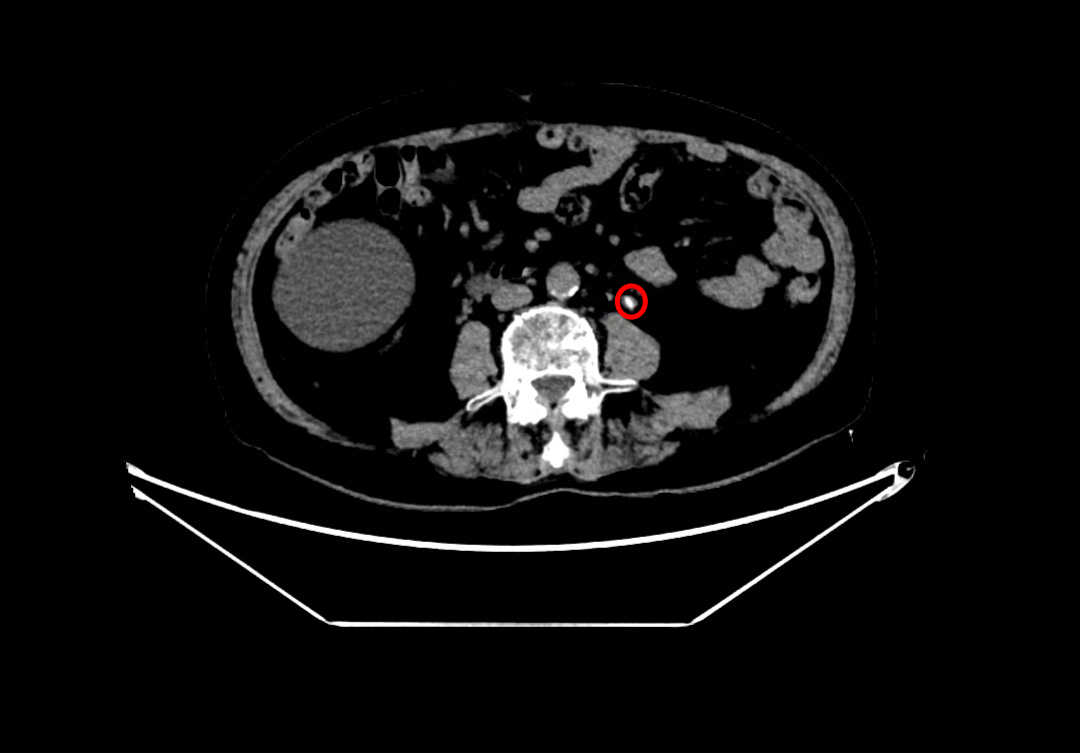

术前左侧输尿管结石

在魏武然主任医师和麻醉手术中心李晓强副主任医师的带领下,泌尿外科和麻醉科医疗团队对何爷爷进行了全面的术前评估,并针对可能出现的各类风险制定了周密的手术方案及应急预案。9月9日,手术如期进行。术中发现患者左肾中下盏存在多发结石,最大约2cm×1.5cm,质地坚硬,同时左输尿管上段见数枚不规则小结石,整体结石负荷大、分布复杂,进一步增加了手术难度。